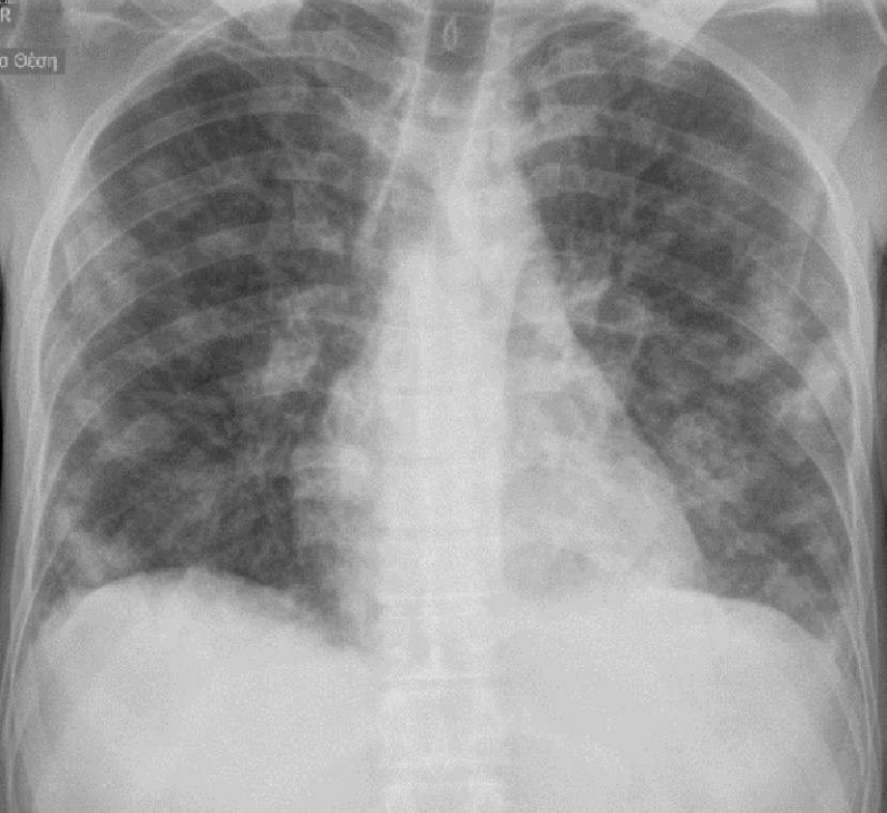

A 34-year-old female patient with a history of IV drug abuse was admitted to the hospital with fever for ten days and worsening dyspnoea for two days. She had tachycardia, fever (41°C) and decreased respiratory murmur.

Her laboratory examinations showed increased Erythrocyte Sedimentation Rate, CRP and WBC with neutrophilia.

What’s the diagnosis ?